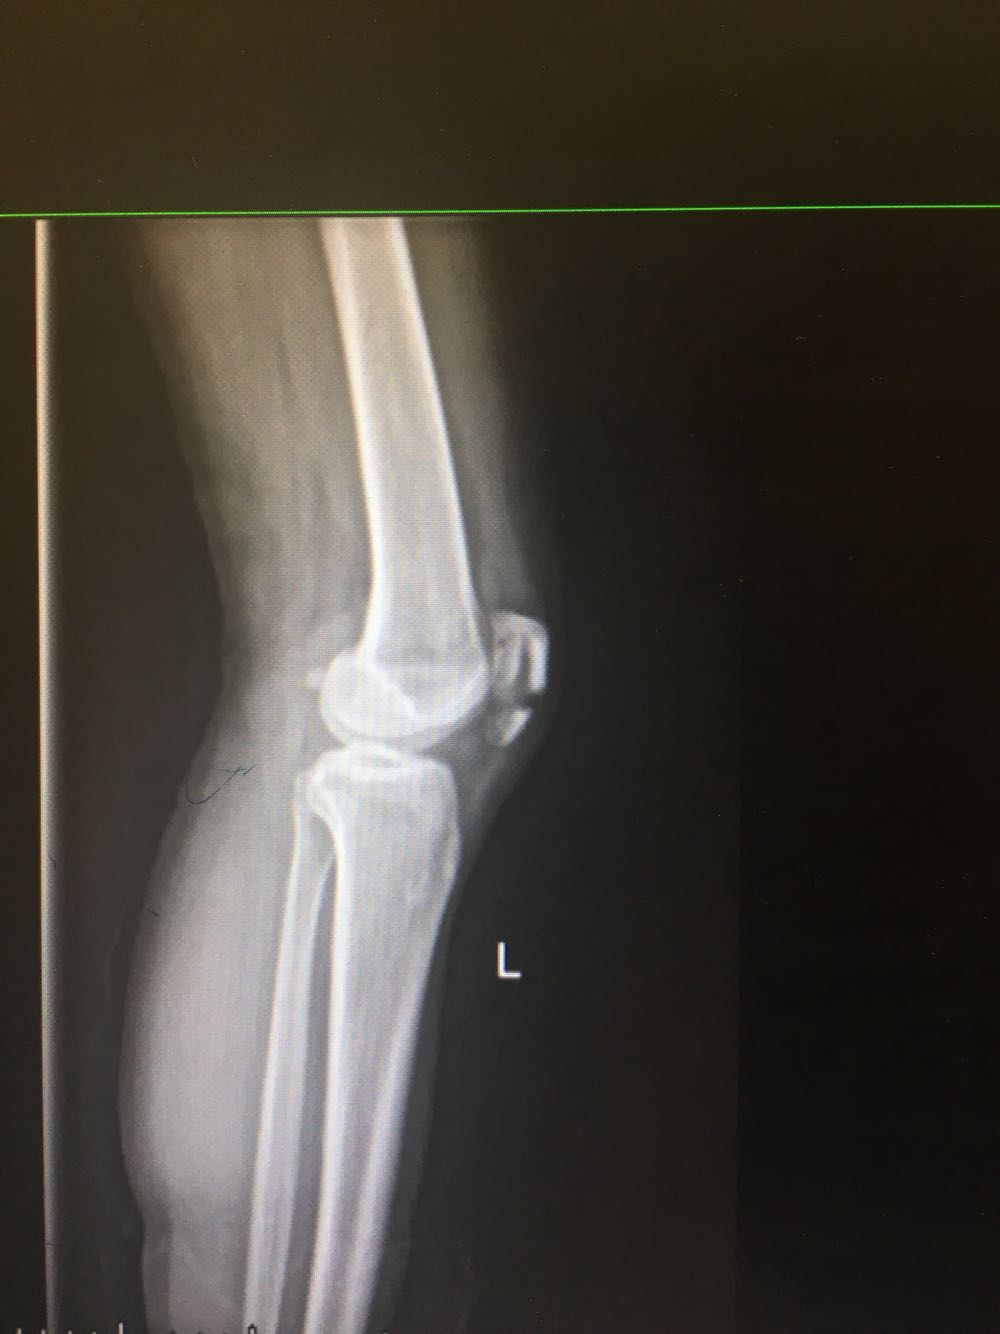

患者,女性,56岁 主诉:外伤后致左膝活动受限12日 现病史:患者于12天前于家中自高处跌到,左下肢着地,即出现左膝关节疼痛,轻度皮损,左膝关节以下活动受限,伴局部肿胀,否认头晕头痛、恶心呕吐等不适,曾至外院就诊,平片示:左侧髌骨粉碎性骨折,予石膏固定,制动,止痛等对症治疗后复查摄片示:骨折愈合不佳,遂至我院就诊,现为进一步诊治收治入院,发病以来,神清,精神可,胃纳夜眠可,二便无殊,体重无明显变化。

查体:左膝关节轻度肿胀,压痛阳性,活动受限,左踝关节运动正常,左足感觉及运动正常。 辅检:膝关节平片

诊断:左侧髌骨骨折 治疗:完善术前检查后行手术内固定